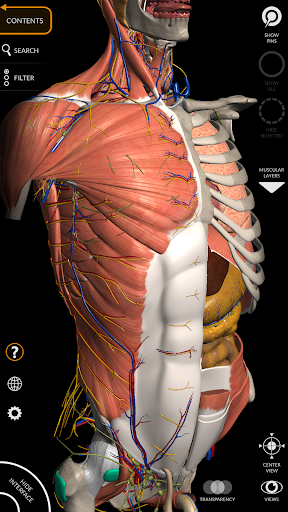

"Anatomy 3D Atlas" memungkinkan Anda mempelajari anatomi manusia dengan cara yang mudah dan interaktif.

Melalui antarmuka yang sederhana dan intuitif, Anda dapat mengamati setiap struktur anatomi dari sudut mana pun.

Model 3D anatomi sangat terperinci dan memiliki tekstur hingga resolusi 4k.

MODEL ANATOMI 3D

• Sistem muskuloskeletal

saraf • Sistem pernapasan • Sistem pencernaan • Sistem urogenital (pria dan wanita) • Sistem endokrin • Sistem limfatik • Sistem mata dan telinga FITUR • Antarmuka yang sederhana dan intuitif • Putar dan perbesar setiap model dalam ruang 3D • Opsi untuk menyembunyikan atau mengisolasi satu atau beberapa model yang dipilih • Filter untuk menyembunyikan atau menampilkan setiap sistem • Fungsi pencarian untuk menemukan setiap bagian anatomi dengan mudah • Fungsi penanda untuk menyimpan tampilan khusus • Rotasi cerdas yang menggerakkan pusat rotasi secara otomatis • Fungsi transparansi • Visualisasi otot melalui tingkat lapisan dari yang superfisial hingga yang terdalam • Dengan memilih model atau pin, istilah anatomi terkait akan muncul • Deskripsi otot: asal, • Tampilkan/ Sembunyikan antarmuka UI (sangat berguna dengan layar kecil) MULTIBAHASA • Istilah anatomi dan antarmuka pengguna tersedia dalam 11 bahasa: Latin, Inggris, Prancis, Jerman, Italia, Portugis, Turki, Rusia, Spanyol, Mandarin, Jepang, dan Korea • Istilah anatomi dapat ditampilkan dalam dua bahasa secara bersamaan PERSYARATAN SISTEM • Android 8.0 atau yang lebih baru, perangkat dengan RAM minimal 3GB Reversi